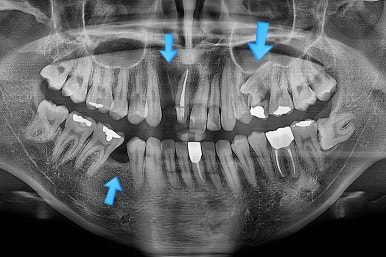

초진 시 입안의 모습입니다.

화살표는 결손 부위, 동그라기믄 유치잔존과 매복치아 부위입니다.

해당 모습을 X-ray로 보면요.

앞니 부러진 부위, 어금니 결손 부위가 명백히 보이죠.

동그라미 부분은 상한 유치가 보이는데, 그 하방으로 영구치가 매복되어 올라오지 못하고 있는 상태였어요.